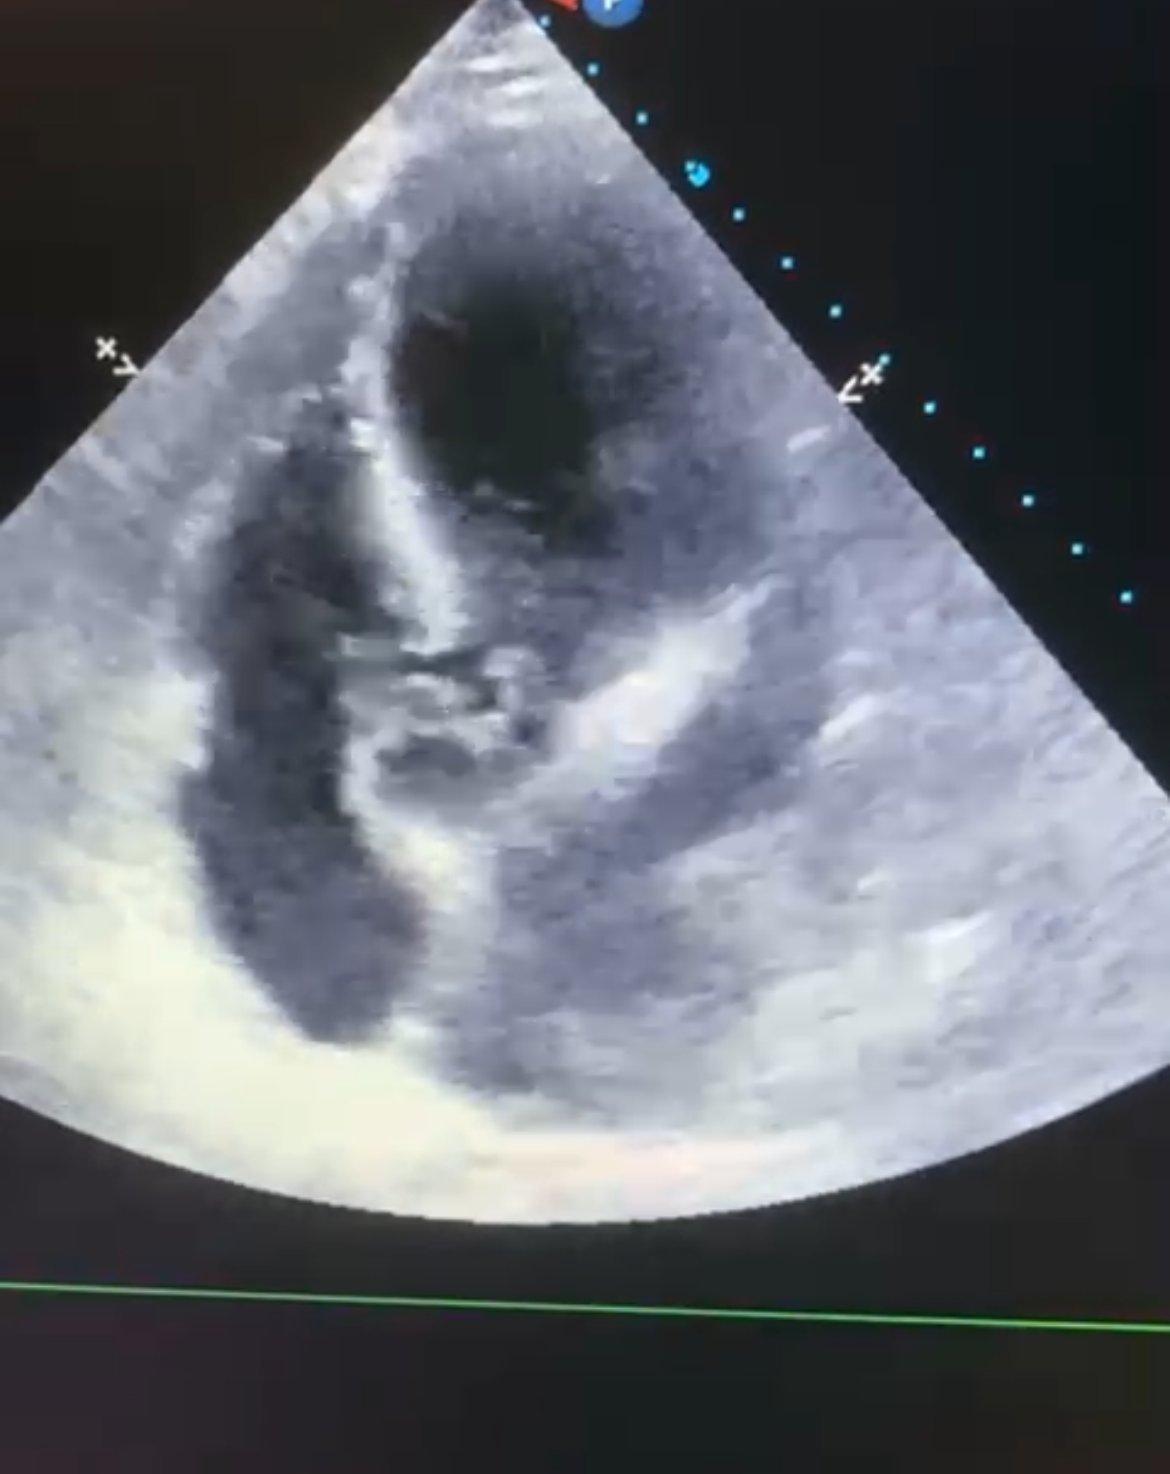

Tras realización de analítica con leucocitosis con desviación izquierda, radiografía de tórax anodina y sin otro foco infeccioso aparente se decide ecocardiografía a pie de cama.

Descripción de los hallazgos ecográficos y las imágenes más relevantes para la resolución del caso

En hemocultivos se detecta Streptococcus anginosus que inicialmente se trata con antibioterapia intravenosa. En TC se visualiza gran verruga en válvula aórtica con insuficiencia severa asociada, por lo que se decide cirugía preferente para recambio valvular.

Ante la presencia de un paciente con clínica inespecífica sin foco infeccioso claro la ecocardiografía a pie de cama ha resultado de gran utilidad para fundamentar la sospecha diagnóstica.